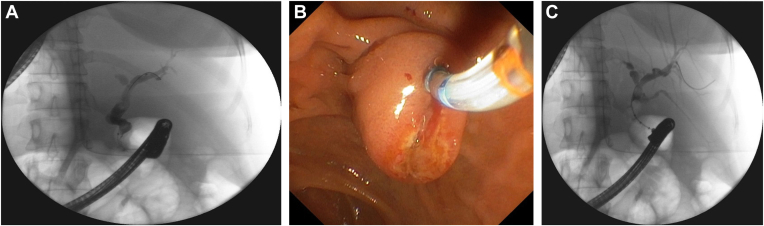

Herein we report a case of a 50-year-old woman presented with epigastric and left upper quadrant pain. Preoperative examination revealed abnormal liver chemistries, situs inversus totalis, and multiple distal common bile duct stones with intrahepatic and extrahepatic bile duct dilatation on abdominal ultrasound. The patient underwent a successful ERCP to relieve biliary obstruction. It was performed while the patient was placed in a supine position with the endoscopist standing on the left side of the patient.

The major emphasis in ERCP is adjusting the patient and endoscopist positions during the procedure. The advantage of the supine position is that the endoscope could easily reach the pyloric ring and, after reaching the duodenum, the papilla could be reached without difficulty.